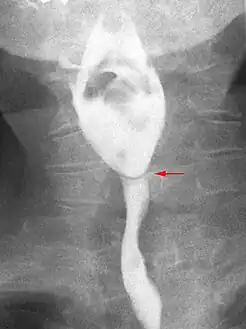

The diagnostic test of choice is a barium swallow.

Esophageal webs are thin 2–3 mm (0.08–0.12 in) membranes of normal esophageal tissue consisting of mucosa and submucosa that can partially protrude/obstruct the esophagus. They can be congenital or acquired. Congenital webs commonly appear in the middle and inferior third of the esophagus, and they are more likely to be circumferential with a central or eccentric orifice. Acquired webs are much more common than congenital webs and typically appear in the cervical area (postcricoid).